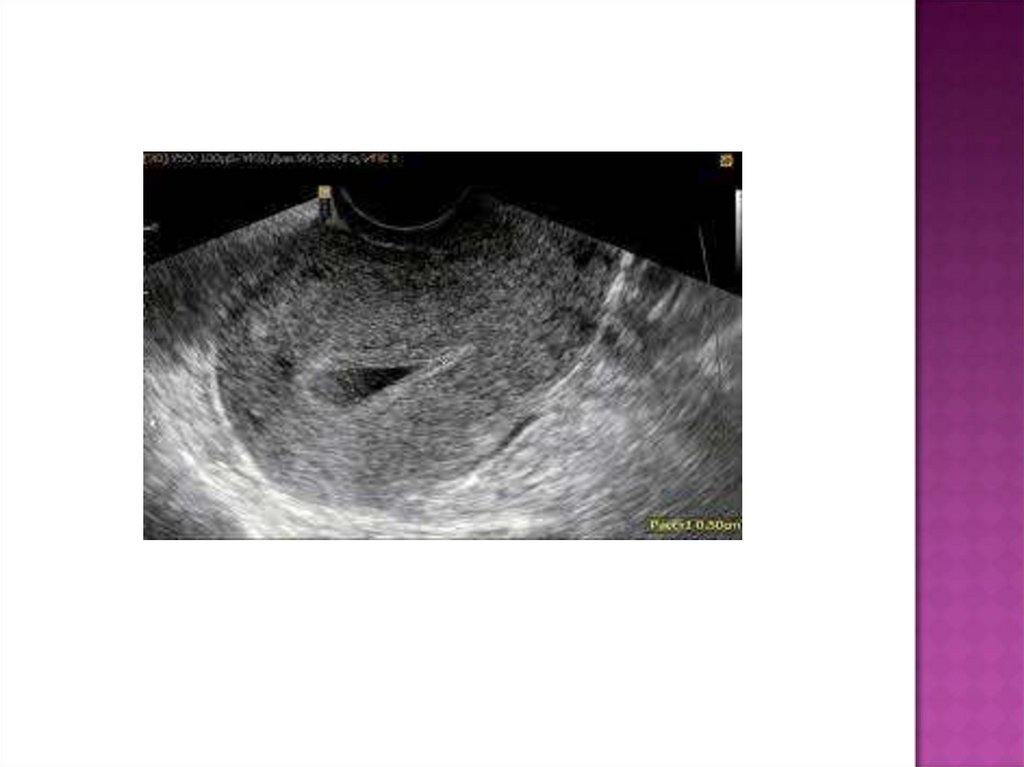

УЗИ:

задержка лохий в полости матки, что происходит в

результате перегиба тела ее к передней брюшной

стенке или вследствие механической закупорки

шеечного канала кровяными сгустками, оболочками,

УЗИ позволяет заподозрить данное заболевание по

сочетанию признаков:

·субинволюция матки;

·расширенная полость матки со множеством точечных

эхопозитивных включений (пузырьки газа);

·выраженный гипоэхогенный контур полости матки

(инфильтрация).

С помощью УЗИ можно обнаружить фрагменты последа

(эхопозитивные наложения на стенках матки).